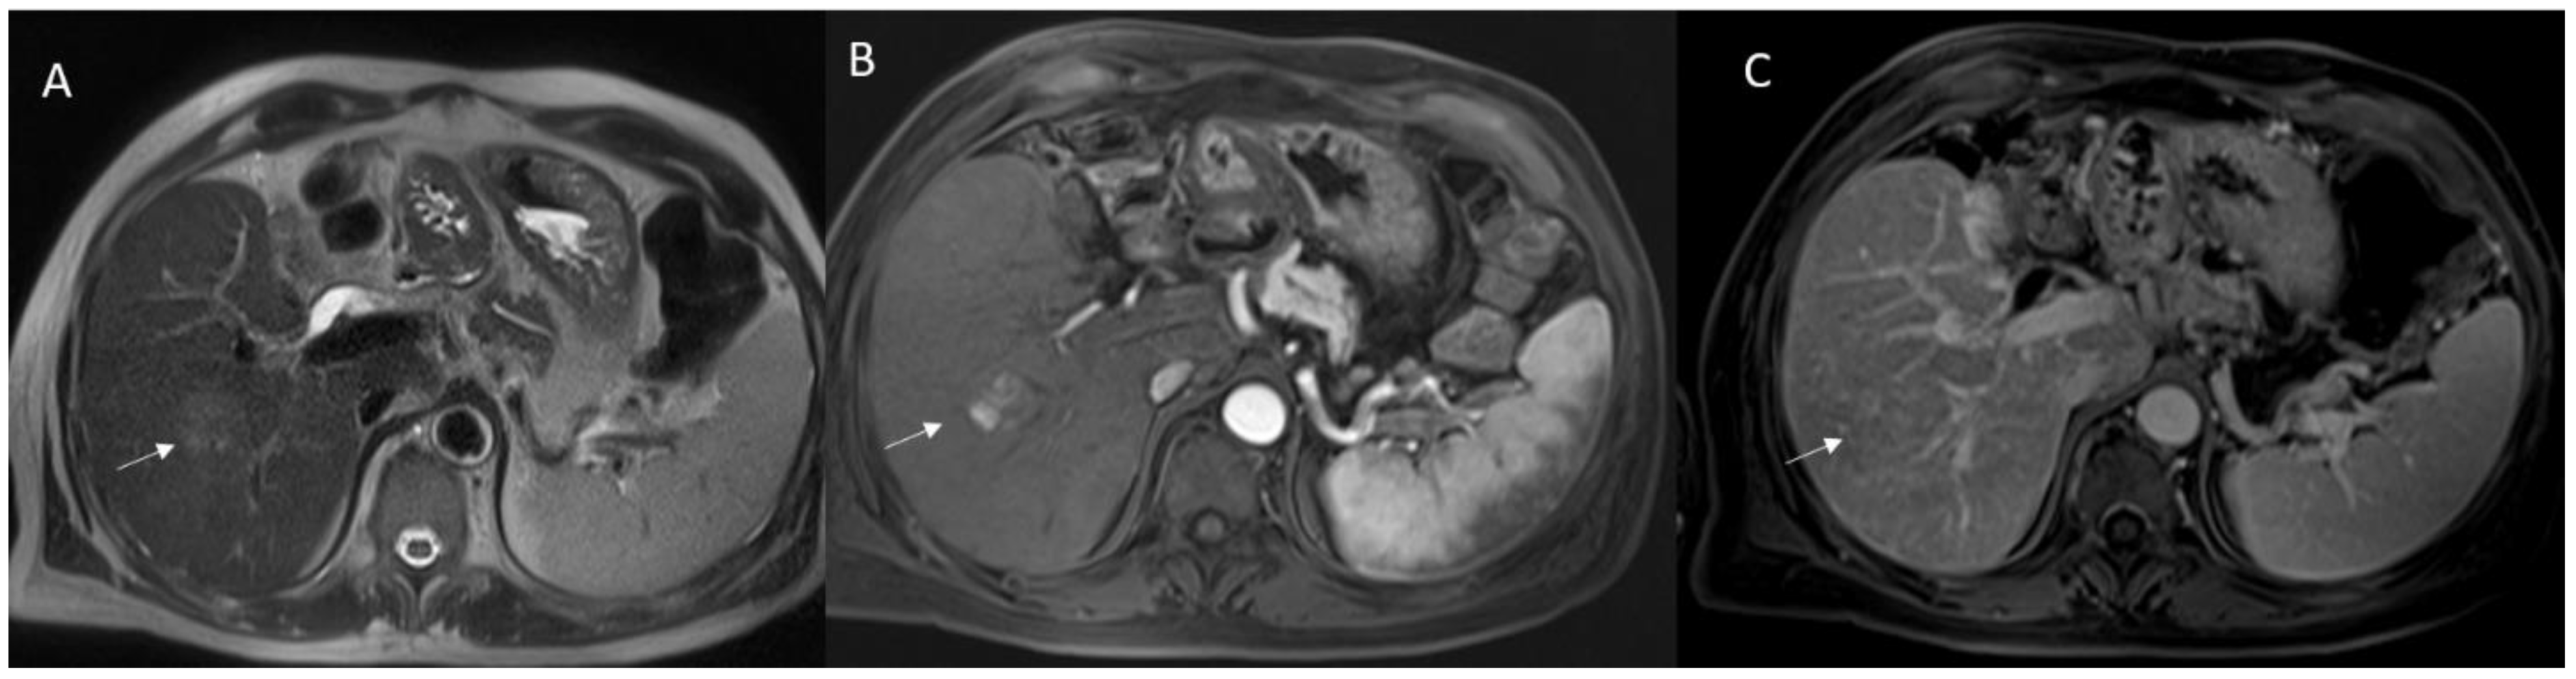

3. Primary Sclerosing Cholangitis

6.5. Diagnostic Management